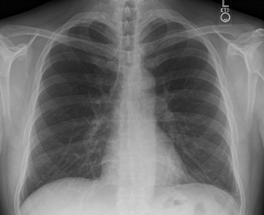

Для фіксації виявлених змін проводять рентгенографію легень (мал. 2 А) – знімають зображення на плівку, що засвічується рентгенівськими променями. На рентгенівській плівці отримують негативне зображення (світлі місця на рентгенівському екрані і навпаки темні – на плівці).

Рентгенологічне дослідження шлунку (мал. 2 В), кишківника (іригоскопія), нирок (екскреторна урографія мал. 2 Г), жовчного міхура (холецистографія мал. 2 Д).

Томографія. Пошарова рентгенографія, що дозволяє отримати зображення окремих шарів досліджуваної ділянки, розташованих на певній глибині. Тіні органів і утворів, розміщених на меншій чи більшій глибині, не накладаються на основне зображення, що дозволяє чітко локалізувати пухлини, запальні інфільтрати. Товщина томографічного шару коливається від 0,5 до 2 см.